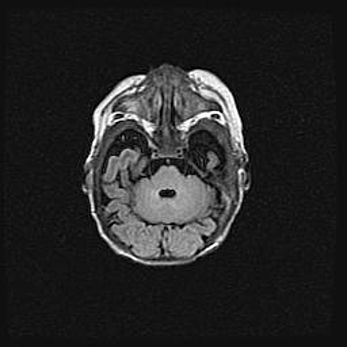

Лейкомаляция с кистозно-глиозной дегенерацией головного мозга.

Возраст: 2 месяца 25 дней

Вес: 6400 г

Окружность головы: 40 см

Срок гестации: 41 неделя

Лейкомаляцию относят к ишемически-гипоксическим повреждениям головного мозга, диагностируемым у новорожденных. При лейкомаляции в головном мозге обнаруживают очаги некроза, возникшие после тяжелой гипоксии и нарушения кровотока. В процессе морфогенеза очаги проходят три стадии: 1) развития некроза, 2) резорбции и 3) формирования глиозного рубца или кисты. Перивентрикулярная лейкомаляция (ПЛ) встречается примерно в 12% случаев среди новорожденных, обычно – у недоношенных детей, причем, частота ее зависит от массы, с которой младенец появился на свет. Наибольшее число малышей страдает лейкомаляцией, если масса при рождении 1500-2500 г.